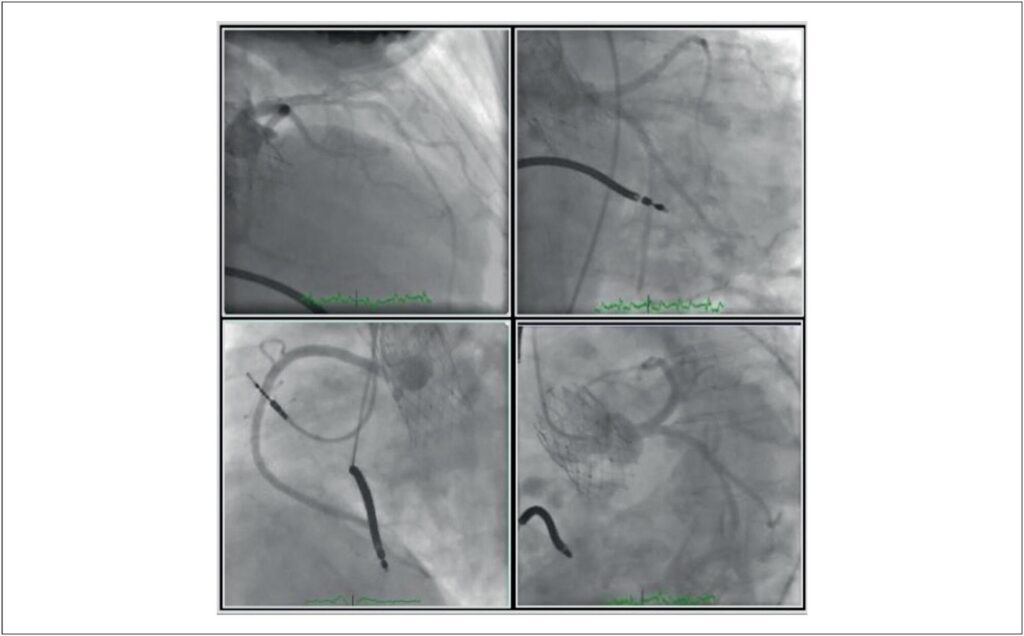

Late Evolution of Takotsubo Cardiomyopathy Following Transcatheter Aortic Valve Implantation

Transcatheter aortic valve implantation (TAVI) is recognized as a first-line treatment for symptomatic patients with advanced aortic stenosis who are at high surgical risk. In inoperable patients with poor prognosis, it carries a risk for complications, such as myocardial infarction due to coronary occlusion, stroke, annular rupture, etc.¹ Takotsubo Cardiomyopathy (TTC) is a syndrome that usually develops in the absence of overt coronary occlusion and signs of alternative diagnosis, including myocarditis. It presents with electrocardiographic changes, increased cardiac biomarkers, and typical echocardiographic findings., In this article, we describe a patient with TTC who previously underwent TAVI and subsequent implantable cardiac defibrillator (ICD) implantation.